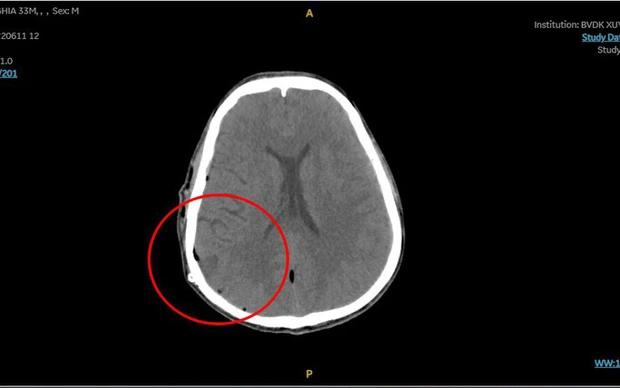

Khối máu tụ khi vào viện gây chèn ép não. Ảnh: BVCC

Ê-kip cấp cứu lập tức đưa anh N. vào chụp CT, kết quả cho thấy sọ có đường nứt nhẹ, xuất huyết não do đứt một mạch máu nhỏ vì chấn thương. Bệnh nhân được đưa vào phòng mổ để cầm máu, hút máu tụ khoảng 150 ml.